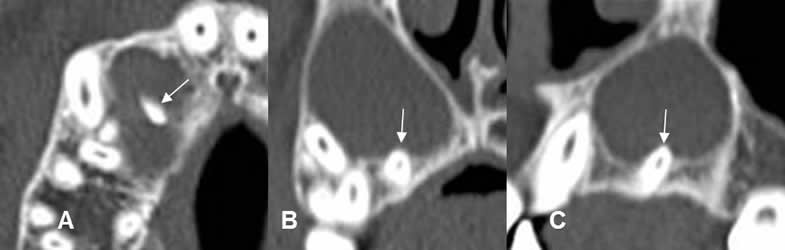

Fig 38. Enfermedad endodental.

A: TAC axial, B: TAC reconstrucción coronal y C: TAC reconstrucción sagital.

Reemplazo de la pulpa de los dientes, por caries extendidas internamente. (Flechas gruesas). Se encuentra perilucencia periapical, por enfermedad endodental.(Flechas delgadas).